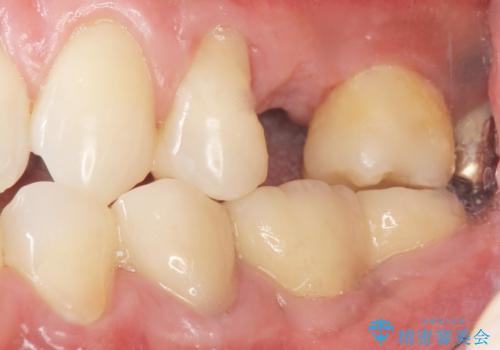

- インプラント治療のついでに、銀の詰め物を白くしたいとご希望された患者様です。

痛みやしみるなどの症状はありませんでしたが、銀の詰め物を除去したところう蝕を認めました。

う蝕を丁寧に除去したのち、セラミックインレーによる修復を行いました。

インプラント埋入まで抜歯後(左上5)の骨の治癒を待つ間に、治療期間の短縮を図り先んじて両隣在歯(左上4,6)のインレー修復を行っております。

インレーの種類:セラミックインレー(e-max press)